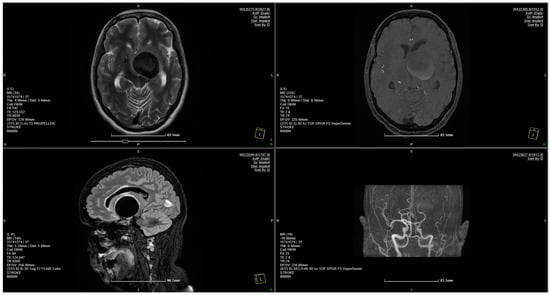

Figure 1.

MRI scan showing a 4 × 3.75 cm giant aneurysm.